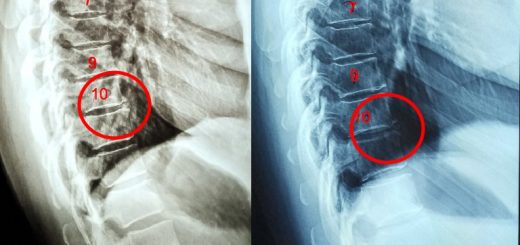

Chronic Lower Back Discomfort caused by Disc Degeneration